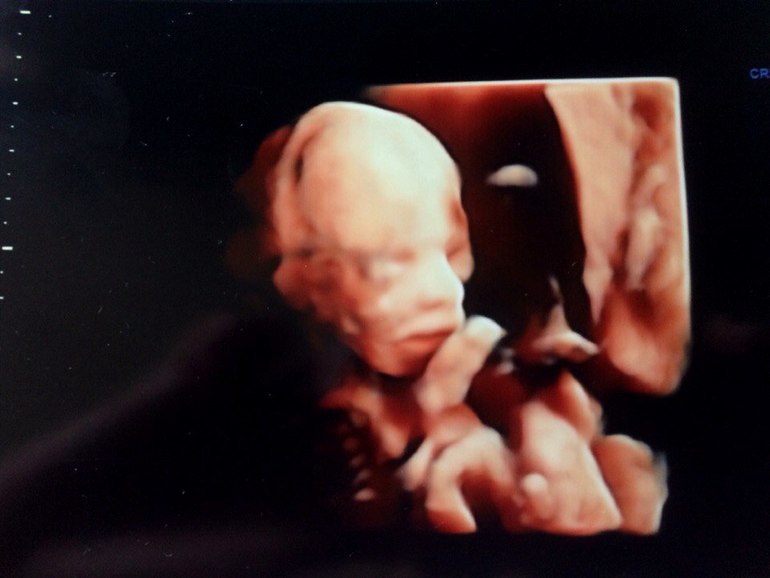

УЗИ 17-18 недель + фото малыша. Узнали пол!

Результаты: УЗИ, КТГ, доплера, скринингаТак, сегодня ходили вместе с мужем на плановое УЗИ. Срок по месячным 17,4, по УЗИ - 18 недель.

Наконец-то сказали пол - мальчик! Не зря мне все снится, что парня родила)

Ну и фото мордашки)